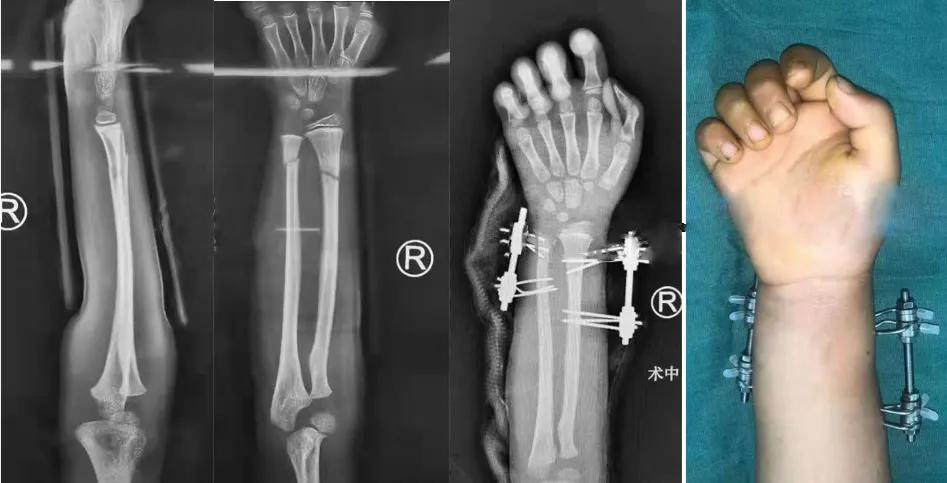

学生: 这两天有两个儿童前臂骨折的病例在骨科同行中引发很大的争议,几乎是一边倒的指责“治疗不当”。一例是11岁的男孩,摔伤后前臂远端骨折,夹板固定11天后再移位,医生做了切开复位内固定。另一例是摔倒致伤的6岁孩子,医生做了微创“创新”的外固定架固定手术,您怎么看?

学生:6岁孩子的前臂骨折,可以用外固定架固定吗?

Slongo的回答是:Good question, but also a wrong question,关键在于“does it make sense”?从技术角度来说,6岁的前臂骨折当然可以做到“外固定架固定”,关键在于, “如果不手术能获得挺好的结果,即便手术效果挺好,为什么要手术呢?”